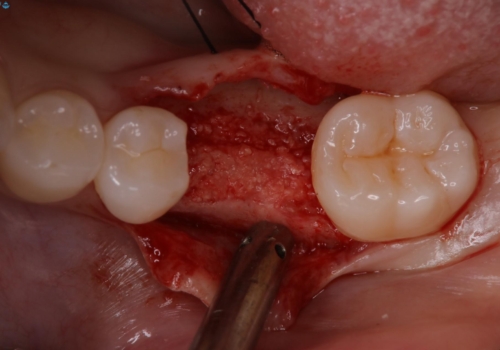

- 他院で抜歯と言われ、今後どうしたらいいのかを相談された患者様です。

抜歯を行った後は、Br、義歯、インプラント、何もしないという選択肢のメリットデメリットを説明させていただき患者様がインプラント治療を希望されたので今回治療させていただくことになりました。

歯のなかったところをインプラント治療を行うことによってまた噛める喜びを感じていただけて良かったと思っております。